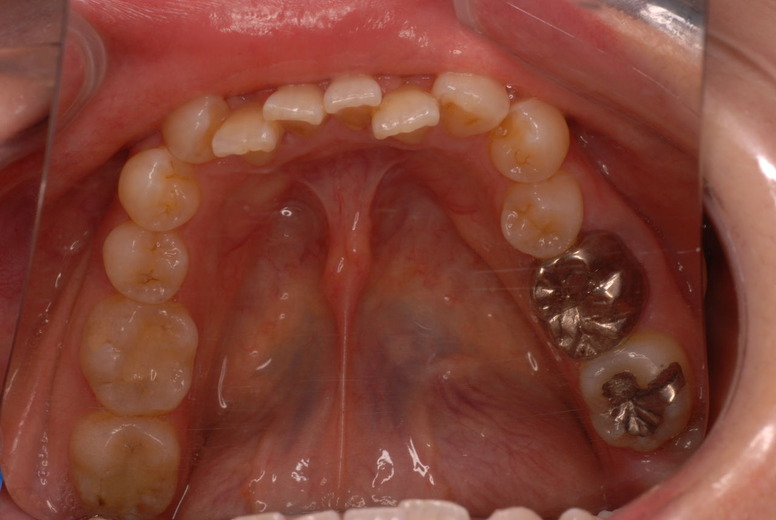

親知らずを取ることを嫌がる方が多いのですが、もし親知らずとその隣の14歳大臼歯の間に虫歯ができたり歯周病を罹患した場合、どれほど治療が大変で再発も起こりやすいか理解できない方がおおいのです。

写真左下の親知らずが痛くなり抜歯しました。その後歯茎を除去して虫歯を露出させる処置を二回ほどしています。

レントゲンでは小さいですが、こう言う虫歯が一番怖いのです。

治療の成功率は極めて悪くすぐ再発しやすいのです。